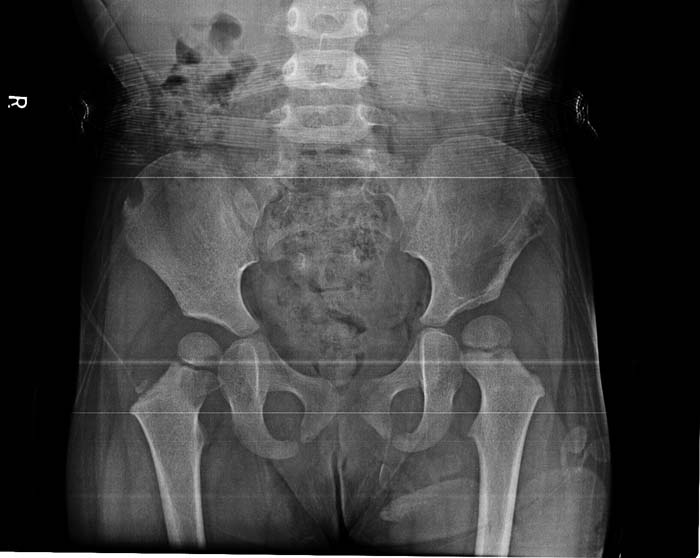

以下是引用yangyudong333在2010-5-21 6:37:00的发言:[br]考虑嗜酸性肉芽肿可能性大。

以下是引用dyqct在2010-5-20 22:24:00的发言:[br]建议做ct、查其它部位、验血查肿瘤标记物等再综合分析。